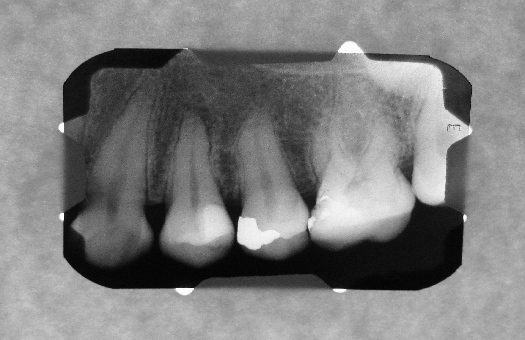

Debido a que trabajamos con la más avanzada tecnologia todas las radiografias digitales pueden ser entregadas/enviadas: Impresas en peliculas radiográficas con formato médico de alto contraste, CD y/o correo electrónico.